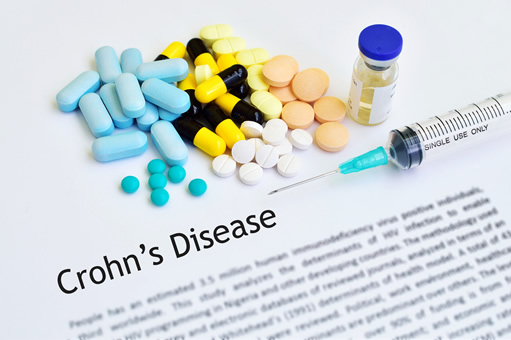

Μόλις επιβεβαιωθεί μία τέτοια διάγνωση, η συντηρητική, δηλαδή η μη χειρουργική της αντιμετώπιση, είναι, κατά κανόνα, η πρώτη επιλογή του θεράποντος γιατρού, εκτός αν, όπως αναφέρθηκε παραπάνω, η κατάσταση του ασθενούς κρίνεται ως επείγουσα ή βαρέως επιπλεγμένη, οπότε η επέμβαση είναι αναπόφευκτη. Η συντηρητική διαχείριση της νόσου περιλαμβάνει πολλές φαρμακευτικές επιλογές τόσο για το αρχικό στάδιο της θεραπείας, όσο και για τα επόμενα, δηλαδή εκείνο της συντήρησης σε μία μη φλεγμονώδη κατάσταση ύφεσης και εκείνο της διατήρησης της ύφεσης και πρόληψης της υποτροπής.

Η επιλογή της πλέον κατάλληλης για την περίσταση θεραπείας συνήθως ανήκει στο θεράποντα γαστρεντερολόγο και γίνεται πάντοτε με γνώμονα το ιστορικό, την ηλικία, τη γενική κλινική εικόνα και το συγκεκριμένο τύπο με τον οποίο εμφανίζεται η νόσος Crohn στον εκάστοτε ασθενή. Η πιο κοινή φαρμακευτική αγωγή για την οξείες εξάρσεις της νόσου είναι ένα κορτικοστεροειδές, όπως η πρεδνιζόνη ή η μεθυλ-πρεδνιζολόνη, σε συνδυασμό με διάφορους αντιφλεγμονώδεις παράγοντες, ενώ ταυτόχρονα είναι αναγκαία η υιοθέτηση συγκεκριμένης διατροφής. Στη συνέχεια, προκειμένου να διατηρηθεί η ύφεση της νόσου και των συμπτωμάτων της, συχνά χορηγούνται στον ασθενή ειδικά ανοσοκατασταλτικά φάρμακα.

Η σύγχρονη ανοσοτροποποιητική αγωγή εναντίον της νόσου Crohn έχει, σήμερα, εμπλουτιστεί με τους ειδικούς βιολογικούς παράγοντες, οι οποίοι σε μέτριας σοβαρότητας και σοβαρές μορφές της νόσου, ιδιαίτερα σε ασθενείς με συρίγγια, έχουν βοηθήσει πολλούς ασθενείς. Αυτά τα ειδικά φάρμακα στοχεύουν συστατικά των κυττάρων της ανοσίας, όπως ένα παράγοντα που λέγεται TNF. Το Infliximab και το Humira, τα πλέον γνωστά και, στις HΠΑ, διαφημιζόμενα ακόμα και στην τηλεόραση, φάρμακα έχουν αλλάξει τη φυσική πορεία της νόσου Crohn. Η κατάχρησή τους, όμως, σε ασθενείς, που φαίνεται ότι θα ωφεληθούν από μία χειρουργική παρέμβαση, δεν είναι η ενδεδειγμένη τακτική. Εξάλλου, τα τελευταία δεδομένα υποστηρίζουν ότι μπορούν να χρησιμοποιηθούν και μετά το χειρουργείο ως προφύλαξη για τον ασθενή, προκειμένου να μην επέλθει σύντομα η έξαρση της νόσου.